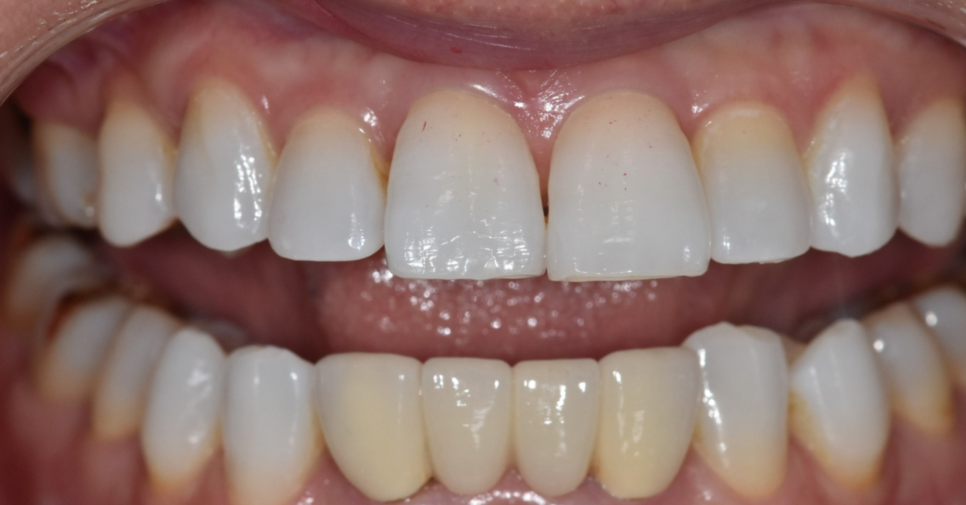

250328 재교정을 목적으로 성인은 진행하기도 하죠.

250328